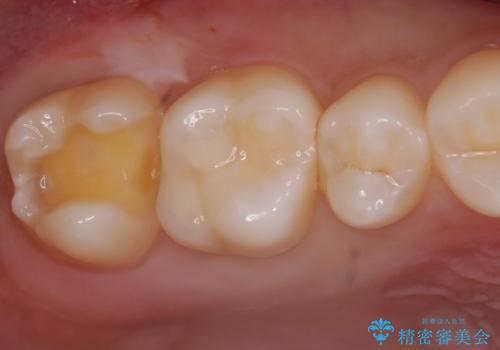

歯と歯の間の虫歯 e-maxインレーで修復

- 歯と歯の間に虫歯が見られたために、拡大鏡下でう蝕を取り除き、e-maxインレーで治療しました。

- e-maxインレー 7.7万円 費用は治療当時の料金となります